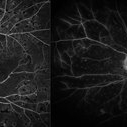

Retinitis Pigmentosa

Bilateral fundus autofluorescence images of retinitis pigmentosa.

Photographer: Olivia Rainey

Imaging device: Heidelberg Spectralis

Condition/keywords: 50 degrees, bilateral, fundus autofluorescence (FAF), hereditary retinal dystrophy, retinitis pigmentosa